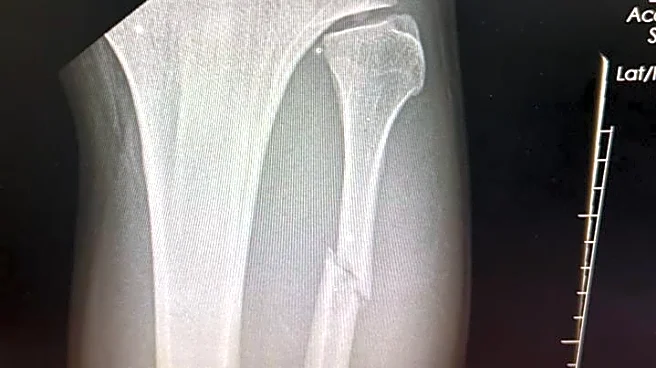

And he did it with a broken leg, snapping his fibula via Sutherland leg kick in the opening frame.